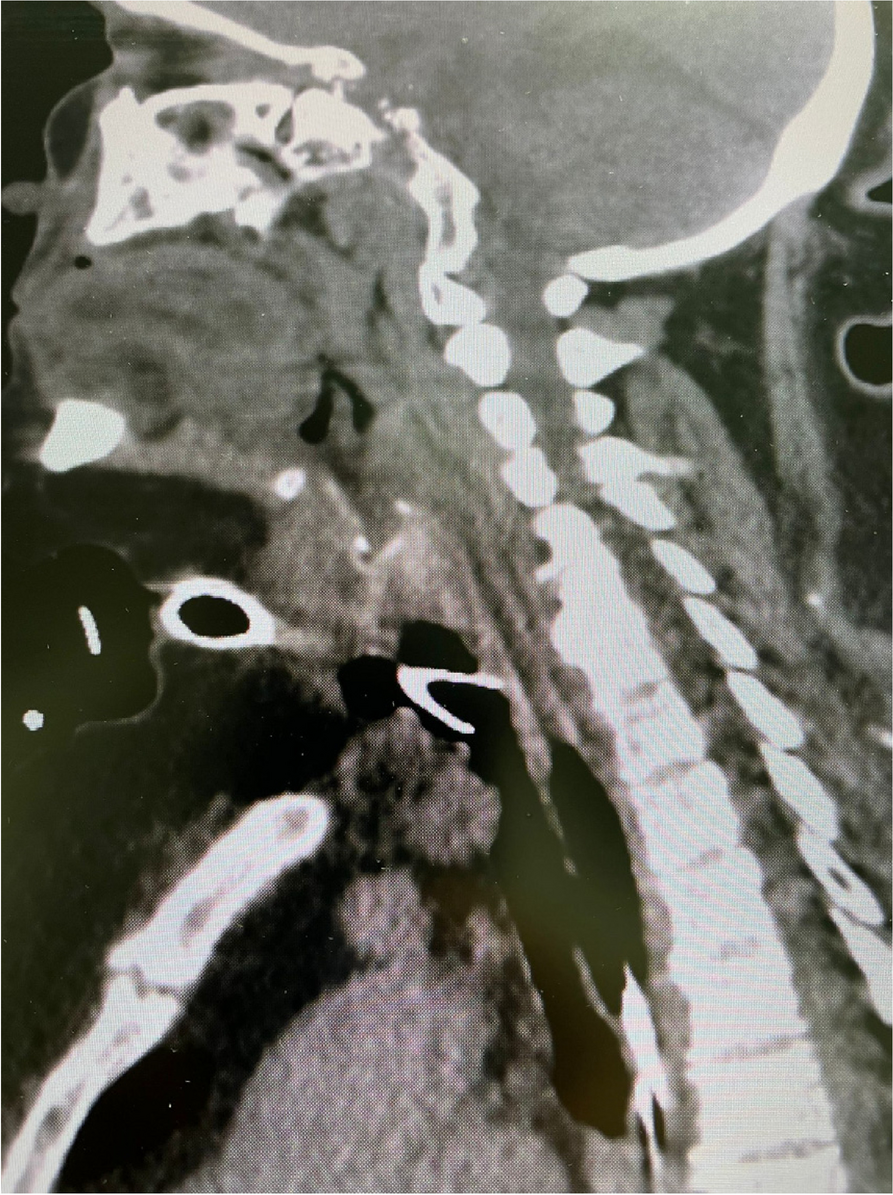

A few hours after the admission in ICU he reported a blunt abdominal pain, mainly on the right side, nausea and the exams showed increased amylase levels, urologists excluded any surgical involvement of pancreatic tissue and suspected a transient sphincter of Oddi dysfunction [3]. After one night in ICU he was transferred to the urology ward due to his clinical stability, even though Amylase peaked at 2340 U/l. Two days later abdominal pain increased to severe, with characteristics of peritonism and increased inflammatory markers. An abdomen-thorax CT scan revealed acute pancreatitis (AP) (Figure 1) and he was transferred to ICU. He started a standard treatment for acute pancreatitis and antibiotic therapy [4].

On postoperative day nine, due to general deterioration of clinical conditions and further anemization that required blood transfusion, he underwent an emergency laparotomy, in which propofol was not used as an anesthetic drug, that found a completely necrotic pancreas. The following day he faced a multi organ failure (MOF) which rapidly led to death. Consent to publish the case report was accorded by the family.

Acute pancreatitis (AP) Is a complex and severe disease with a high mortality rate [4]. Propofol, is a common anesthetic drug which is widely used in daily practice for sedations and general anesthesia [5], few cases of Propofol Induced AP have been published, in which the diagnosis has been made excluding more common causes [6].

In fact, Propofol is listed as a possible cause of AP, class Ib, based on the classification of Badalov et al. [7]. Following the scheme proposed by the systematic review by Haffar et al for Propofol induced AP [6] we could confirm that our hypothesis is plausible. He satisfied the American College of Gastroenterology criteria for AP [8,9] and it is classified as severe acute pancreatitis according to the Revised Atlanta Classification with peripancreatic necrotic fluid collection [10]. Marshall score [11] after admission was two and Naranjo et al [12] probability scale for drug adverse reaction was three, meaning that the adverse reaction is possible. Latence according to Badalov et al [7] has been short or intermediate. Exclusion of other plausible causes, timing of pancreatitis symptoms and previous cases in literature support our hypothesis of propofol induced pancreatitis.

Fig. 1 (abstract A21).

See text for description

Bild vergrößern